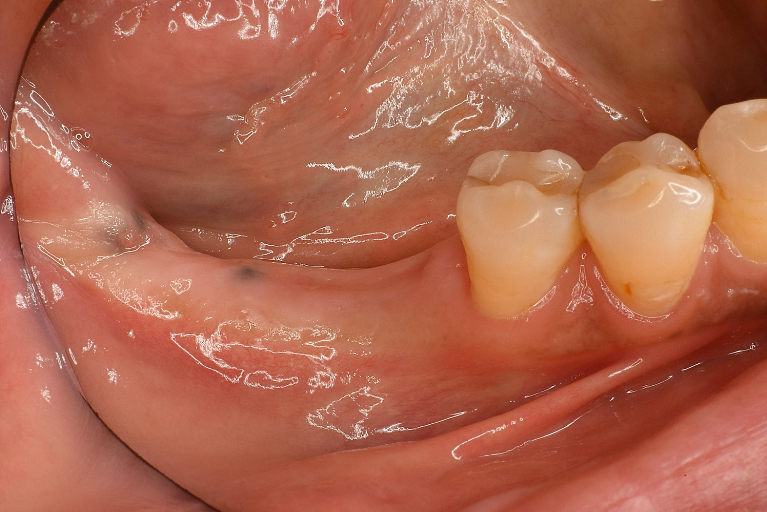

術前

術中

術後

| 治療名 | GBRとインプラントを行った症例 |

|---|---|

| 治療説明 | インプラントを埋入予定の部位において、骨の吸収が見られたため、インプラント埋入と同時に小規模な骨造成(GBR)を行いました。治癒期間を経て、最終的にセラミックの上部構造を装着し、自然な見た目としっかりとした噛み合わせを回復しました。 |

| 治療回数・期間 | 6ヶ月 |

| 副作用とリスク | インプラント治療は、入れ歯やブリッジに比べて治療期間が長くなる傾向があります。骨造成が必要な場合は、さらに治療期間が延びることがあります。 また、手術後には一時的な違和感や痛み、腫れ、出血などが生じる場合がありますが、通常は2日〜1週間ほどで落ち着きます。 |

| 料金(税込) | GBR〈小規模骨造成〉:110,000円 インプラント一次手術:220,000円 二次手術:55,000円 上部構造〈セラミック〉:165,000円 合計:550,000円 |